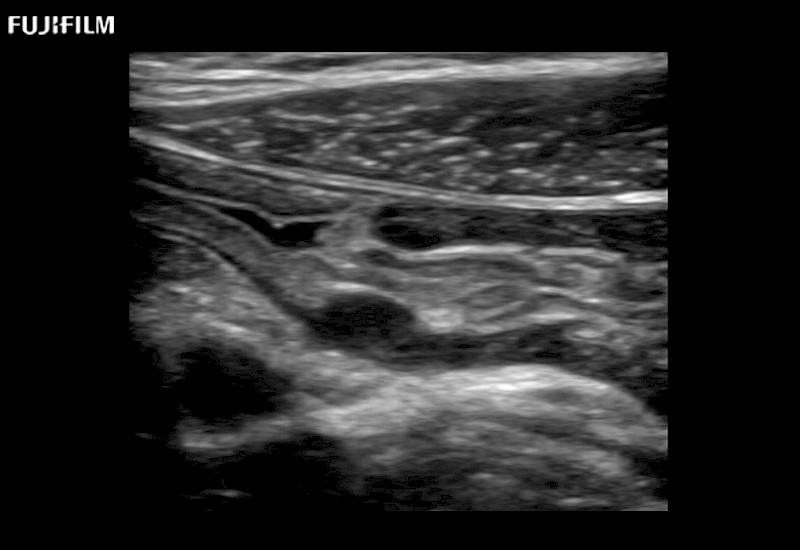

The ARIETTA 750 incorporates all of the proven technologies and functions that medical professionals have come to expect from Fujifilm Healthcare.

ARIETTA 750 is the definitive diagnostic ultrasound solution for any clinical setting - Private Office, Imaging Center, or Hospital. The ARIETTA platform provides the ultimate in clinical performance with its state-of-the-art features and large user-friendly display.

The ARIETTA 650 DI combines trusted Fujifilm Healthcare technologies and features tailored for surgical oncology.

Designed to meet the demands of surgeons, the ARIETTA 650 DI offers precise guidance. Its advanced capabilities and large, intuitive display offer accurate and efficient care in operating rooms and specialized surgical settings.